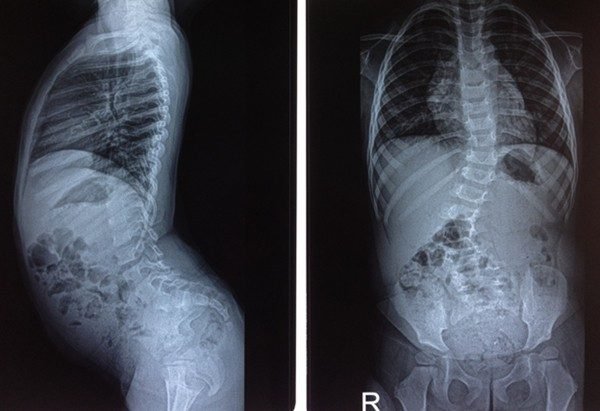

Phẫu thuật chỉnh vẹo cột sống là một phương pháp điều trị bệnh vẹo cột sống, một tình trạng mà cột sống bị uốn cong, gây ra đau lưng và khó khăn trong việc di chuyển. Phẫu thuật chỉnh vẹo cột sống được thực hiện để cải thiện chức năng và giảm đau cho bệnh nhân.

Phẫu thuật chỉnh vẹo cột sống là một phương pháp điều trị bệnh vẹo cột sống bằng cách sử dụng các kỹ thuật phẫu thuật để chỉnh sửa độ cong của cột sống. Phẫu thuật này có thể được thực hiện thông qua các phương pháp truyền thống hoặc thông qua các kỹ thuật tiên tiến hơn như phẫu thuật robot.

Phẫu thuật chỉnh vẹo cột sống được chỉ định cho các trường hợp vẹo cột sống nghiêm trọng, gây ra đau lưng và khó khăn trong việc di chuyển. Nếu bệnh nhân không phản ứng tốt với các phương pháp điều trị không phẫu thuật, phẫu thuật chỉnh vẹo cột sống có thể được xem xét.